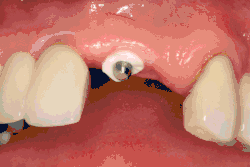

- формирователь десны (также: формирователь десневой манжеты, ФДМ; жарг. хилинг от англ. healing abutment досл. «опора для заживления; заживляющая опора»)

- абатмент (от англ. abutment досл. «опора») — прикрепляемая к имплантату часть конструкции, служит опорой для будущей коронки или протеза

В неразборном имплантате (употребляются также термины: одноэтапный имплантат, моноимплантат) внутрикостная часть имплантата и абатмент обычно изготовлены из единого куска материала. После установки имплантат своей наддесневой частью сразу оказываются в контакте с полостью рта. На усмотрение доктора устанавливается формирователь десны либо временная коронка. В случае установки временной протезной конструкции (коронки, моста или полного протеза) на имплантат не позднее трёх дней после имплантации говорят о немедленной нагрузке.